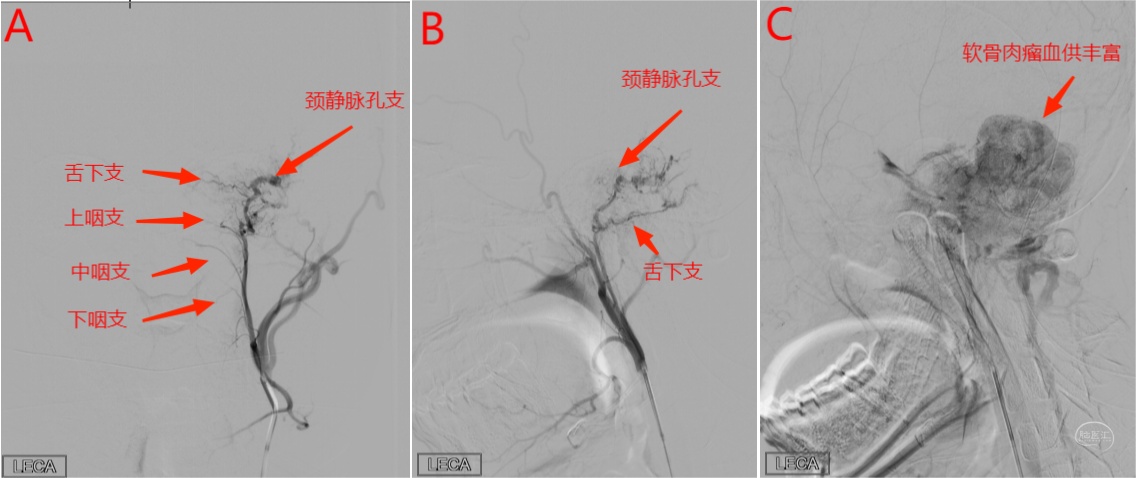

左侧后颅窝软膜肉瘤患者进行术前造影及栓塞,咽升动脉神经脑膜支(颈静脉孔支)为主要供血动脉。

图 21 左侧颈外动脉造影正位(A)、侧位动脉早期(B)及侧位静脉期(C)显示左侧后颅窝病变血供丰富,由左侧咽升动脉神经脑膜支的舌下支和颈静脉孔支供血,引流入颈内静脉和经髁后静脉引流入椎旁静脉丛。同时可见上、中、下咽支显影。

图22 左侧咽升动脉神经脑膜支微导管超选侧位造影(D)显示供血动脉舌下支和颈静脉孔支,颗粒栓塞后经左侧咽升动脉神经脑膜支微导管超选侧位造影(E)显示病变血供明显减少,造影剂返流进入咽升动脉主干和咽支。